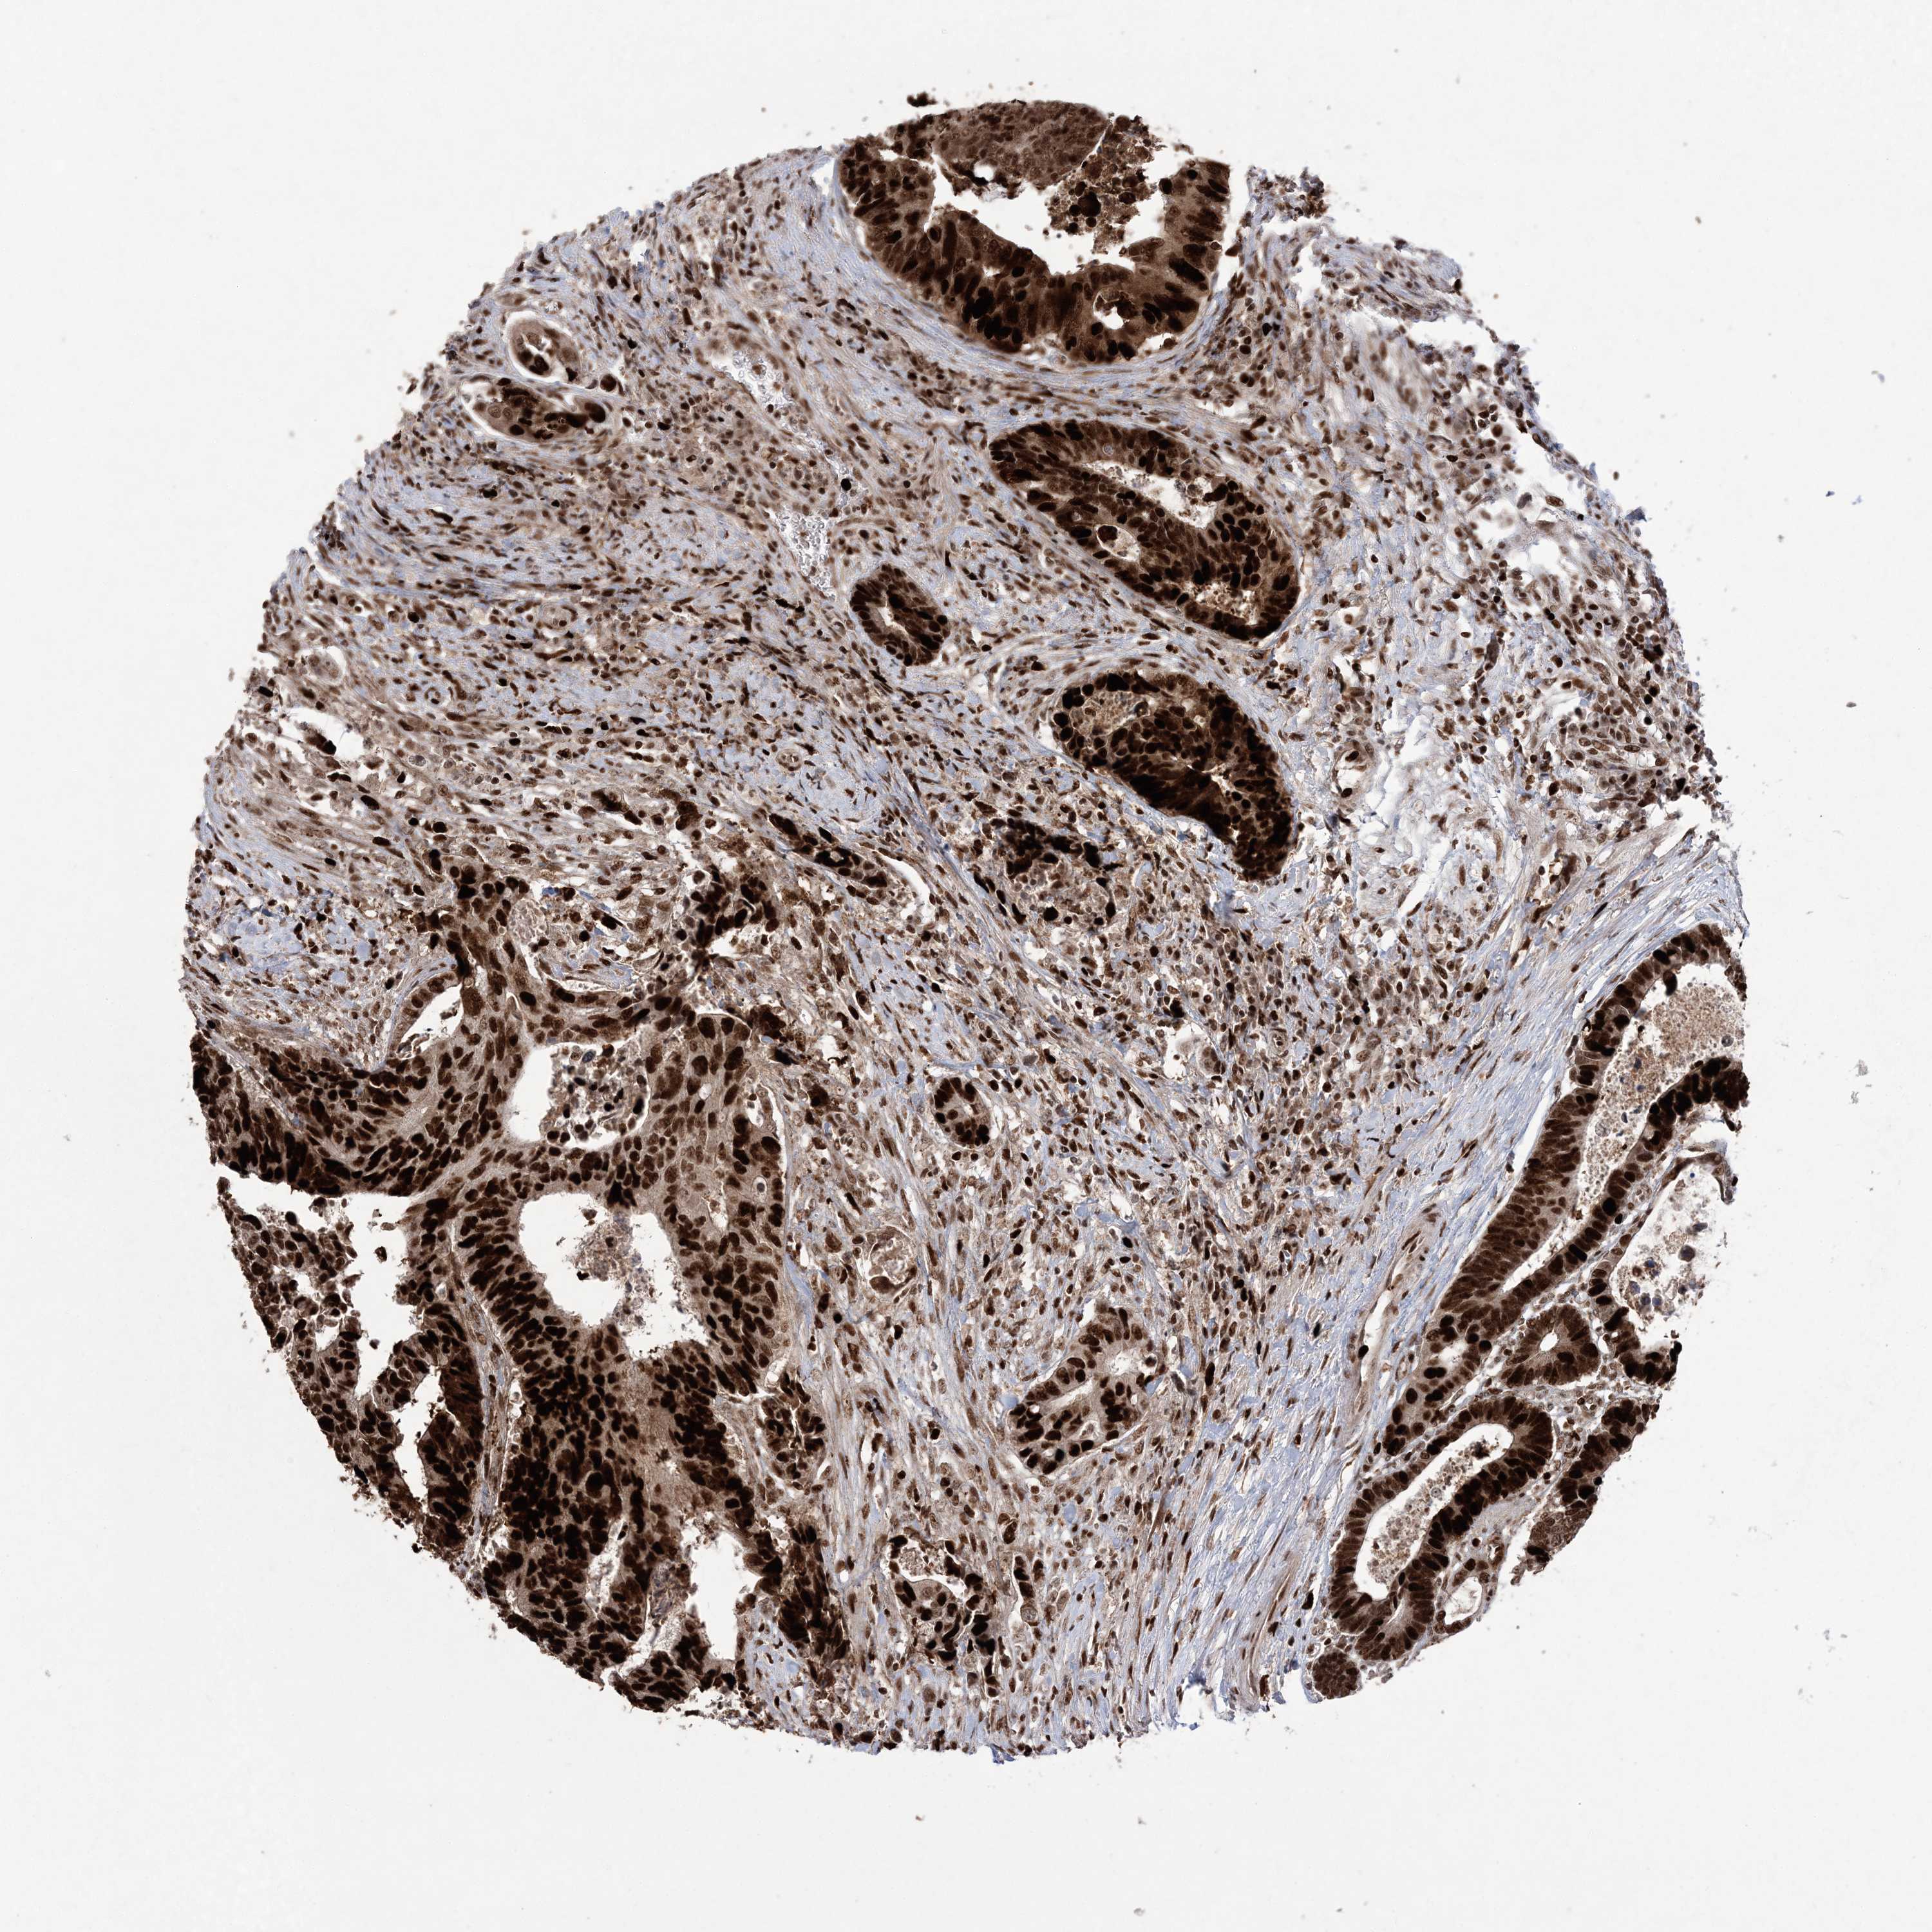

CANCER COLORECTAL CANCER Show tissue menu

COAD TCGA COAD VALIDATION READ TCGA READ VALIDATION PROTEIN COAD CPTAC PROTEIN EXPRESSION

Colorectal cancer

Human cancer

Colon adenocarcinoma